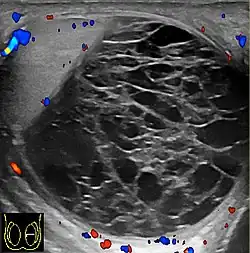

However, these patterns, except the latter one, may be considered as non-specific as heterogeneous echotexture and shadowing calcification can also be detected in malignant testicular tumors. The onion peel pattern of epidermoid cyst [Fig. 10] correlates well with the pathologic finding of multiple layers of keratin debris produced by the lining of the epidermoid cyst. This sonographic appearance should be considered characteristic of an epidermoid cyst and corresponds to the natural evolution of the cyst. Absence of vascular flow is another important feature that is helpful in differentiation of epidermoid cyst from other solid intratesticular lesions.

At ultrasound, the findings of acute epididymitis include an enlarged hypoechoic or hyperechoic (presumably secondary to hemorrhage) epididymis [Fig. 20a]. Other signs of inflammation such as increased vascularity, reactive hydrocele, pyocele and scrotal wall thickening may also be present. Testicular involvement is confirmed by the presence of testicular enlargement and an inhomogeneous echotexture. Hypervascularity on color Doppler images [Fig. 20b] is a well-established diagnostic criterion and may be the only imaging finding of epididymo-orchitis in some men.

Doppler ultrasound of the scrotum of the same case, in the axial plane, showing orchitis (as part of epididymo-orchitis) as hypoechogenic and slightly heterogenic left testicular tissue (right in image), with an increased blood flow. There is also swelling of peritesticular tissue.